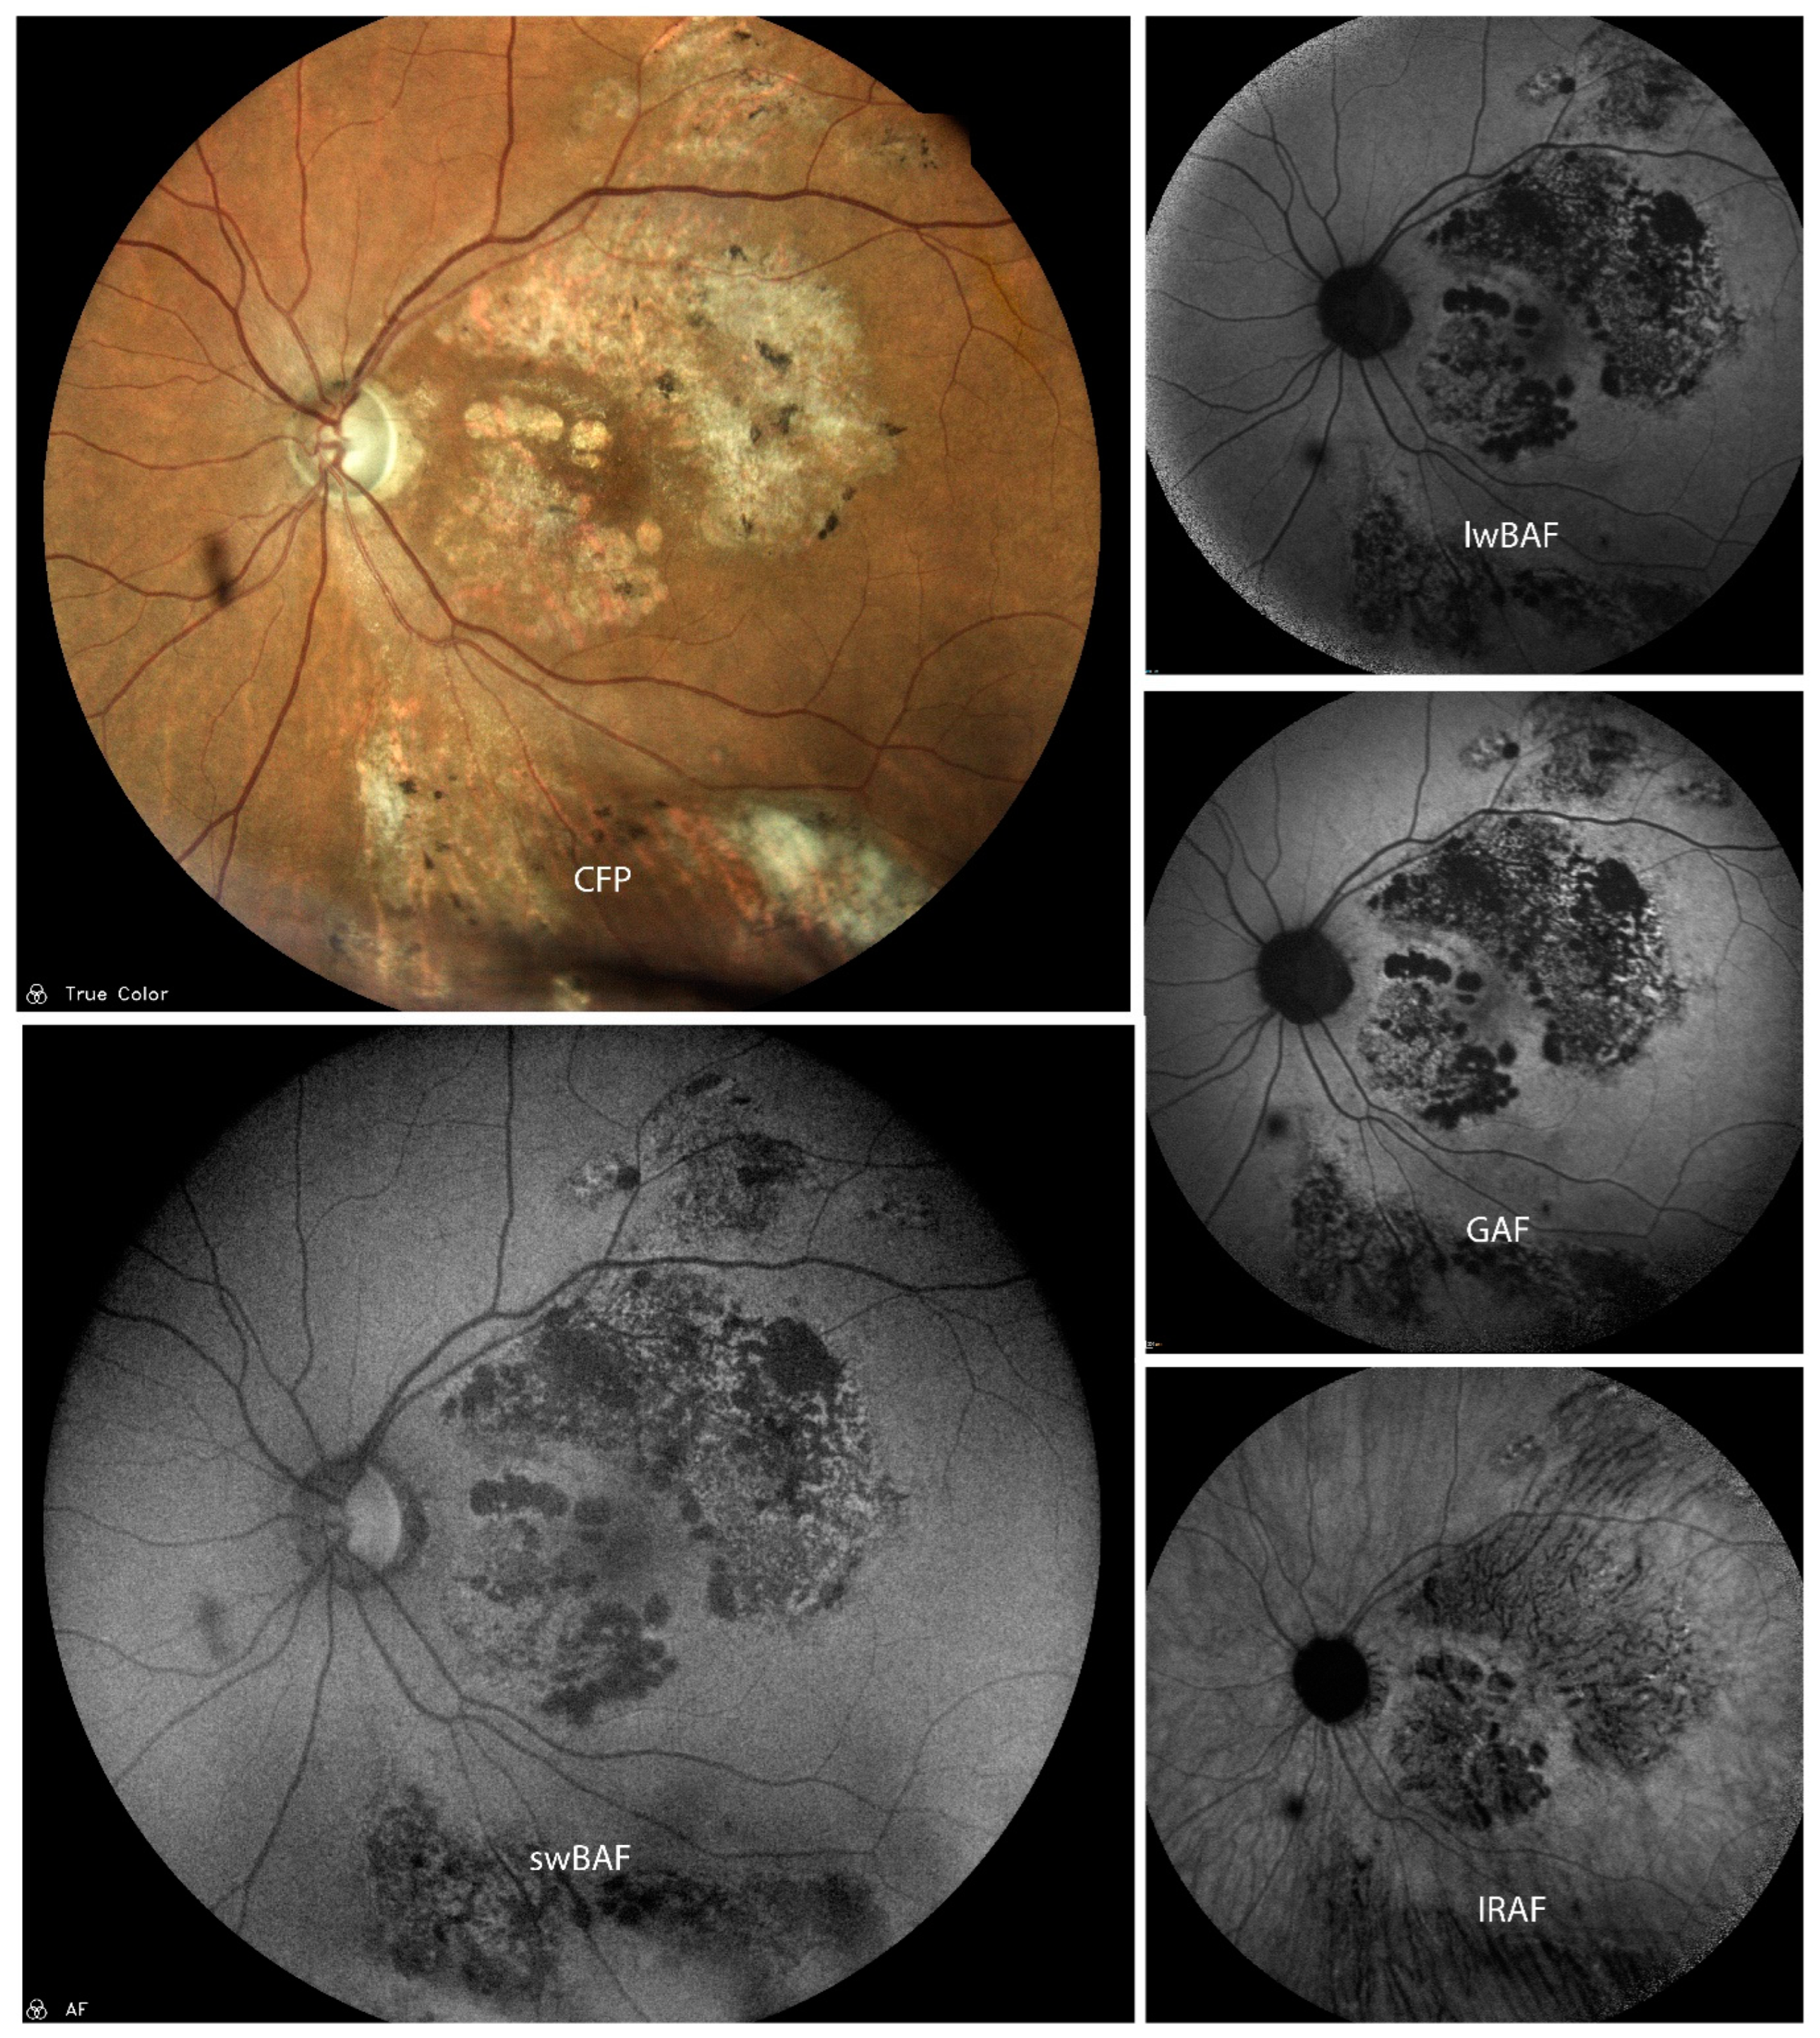

3.2.1. Cytomegalovirus (CMV) Retinitis

- Wintergerst, M.W.M.; Merten, N.R.; Berger, M.; Dysli, C.; Terheyden, J.H.; Poletti, E.; Holz, F.G.; Schäfer, V.S.; Schmid, M.; Ach, T.; et al. Spectrally resolved autofluorescence imaging in posterior uveitis. Sci. Rep. 2022, 12, 14337. [Google Scholar] [CrossRef]